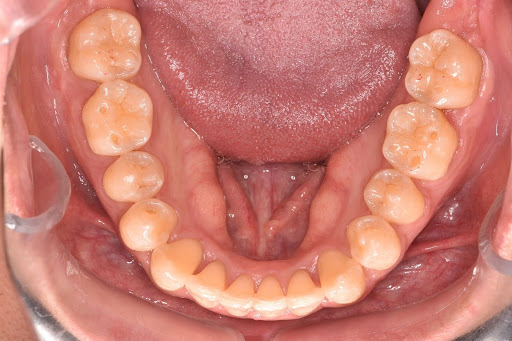

【症例写真】

ガタつきのある歯並びも、マウスピース矯正でここまできれいに整えることが可能です。

<Before>